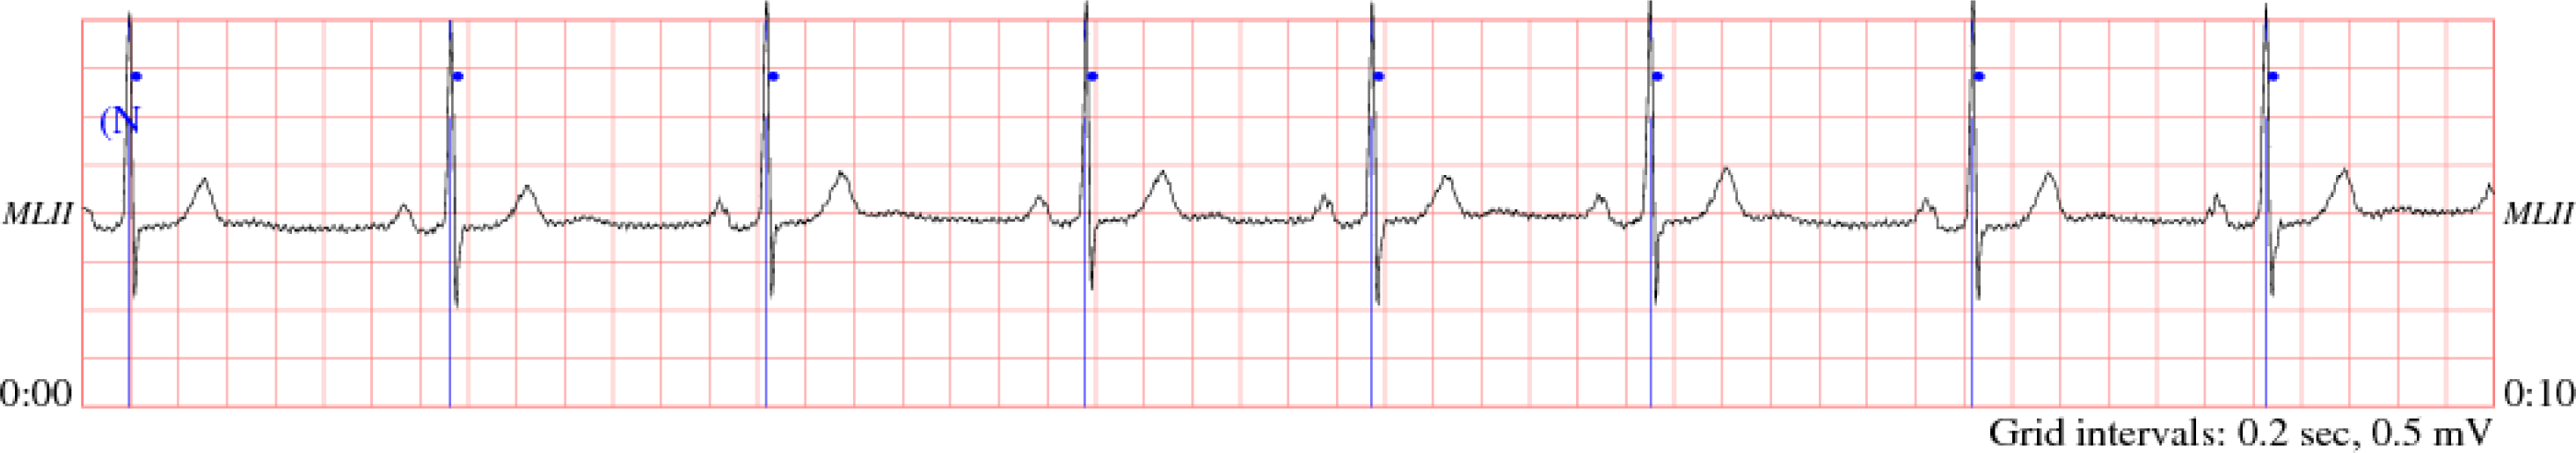

The two types of sampling data used in this experiment are ECG data and body temperature. A normal ECG data is a continuous stream of data with a sample rate of several milliseconds, thereby generating a large dataset within several seconds. The body temperature is sampled several times per day, consisting of three times in the morning, afternoon and night respectively. The ECG sampling data is adopted from PhysioBank’s 123rd record with MLII signals in the MIT-BIT Arrhythmia Database. The data is contained using text formatting, as shown in Figure 8 [12].

The ECG data are loaded on the PDA side, transferred to float type and recorded in the RAM. This sampling data was sampled every three milliseconds, and there are 333 ECG data samples per second. The original ECG graph is shown in Figure 9 [13].

Figure 9. The original ECG data graph.